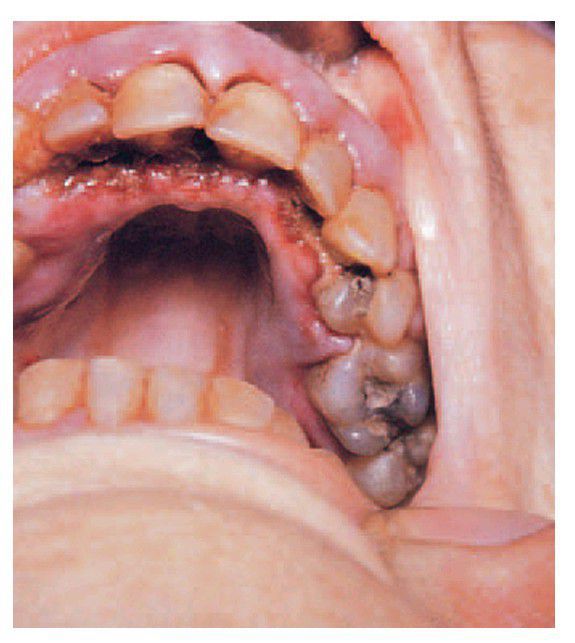

Acute myelocytic leukaemia.

The gingivae are grossly swollen and purplish; in addition there is ulceration along the palatal aspect of the anterior teeth resulting from the increased susceptibility to infection.